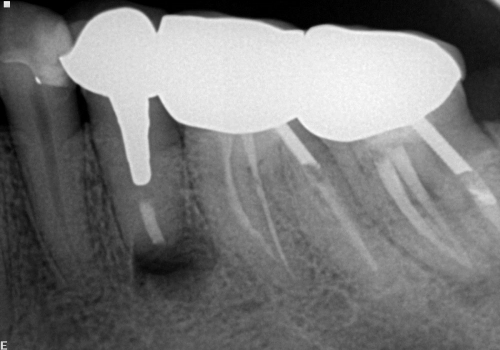

Endodontik müalicə (kanal müalicəsi) həyata keçirilən dişlərdə, kök kanallarının mürəkkəb konfiqurasiyası, yalnış və ya yetərsiz müalicə metodunun tətbiqi, bəzən də həkim səhvi/ehtiyatsızlığına bağlı olaraq təkrar iltihablanma – apikal ostit meydana çıxa bilir. Çox zaman bu tip iltihabi proseslər kliniki olaraq şikayətlərə səbəb olmadığından, zaman keçdikcə miqyasını genişləndirərək iltihab mənşəli odontogenik kistlərin yaranmasına gətirib çıxarır.

Bu zaman bəzi hallarda kanal müalicəsinin yenidən icrası (endodontik reviziya) mümkün olsa da, bir çox hallarda bu və ya digər səbəbdən həyata keçirilməsi mümkün olmur. Bu zaman əsas tətbiq edilən müalicə metodu dişi çəkməmək şərti ilə, iltihab ocağının uzaqlaşdırılmasını təmin edən – diş kökünün rezeksiyası metodudur. Bu əməliyyat vasitəsilə iltihab ocağı diş kökü ilə birlikdə kənarlaşdırılır və kök kanalları xüsusi metodla yenidən işlənir və doldurulur. Əməliyyat əsasən yerli ağrısızlaşdırma altında, xüsusi böyüdücü vasitənin tətbiqi ilə həyata keçirilir.